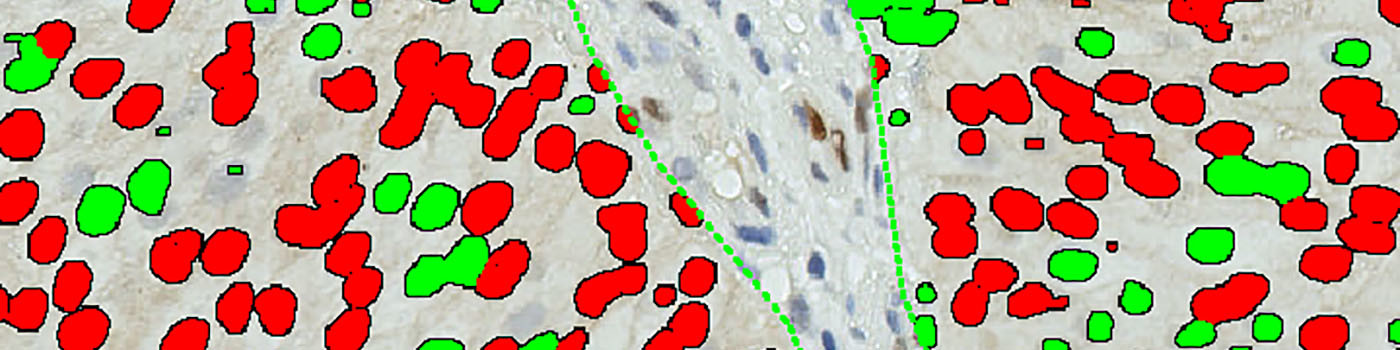

The method used for computing the Cyclin D1 expression is started by detecting nuclei using a novel pattern recognition method adapted from Dahl et al, see [6], which is followed by a step that separates adjacent nuclei, see [7]. The detected nuclei are classified as either positive or negative based on a computation of DAB intensity, obtained using color deconvolution.

This leads to the calculation of the positive area fraction, as the area of positive nuclei divided by the total area of nuclei (within the outlined ROI). This is followed by the measurement of the average DAB intensity across all positive nuclei, which is subtracted from 255, to associate higher values with a high staining intensity, which is more intuitive. The expression is then calculated by multiplying the intensity with the area fraction.

The actual implementation of the pattern recognition allows the user to choose settings for nuclear detection sensitivity and classification into positive and negative, in order to account for differences in local staining protocols.

This APP requires manual outlining of tumor regions.